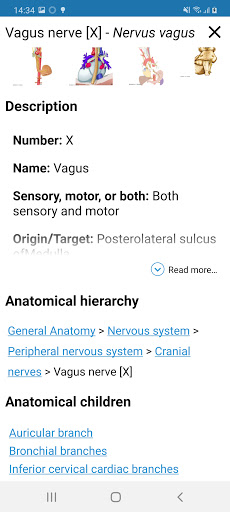

* تحسين رؤية تعريفات الأجزاء التشريحية

* تصفح بين الأجزاء التشريحية باستخدام روابط الوصف

- يتم الآن عرض المصطلحات المتعلقة بالهيكل التشريحي في عرض التفاصيل - تمت إضافة